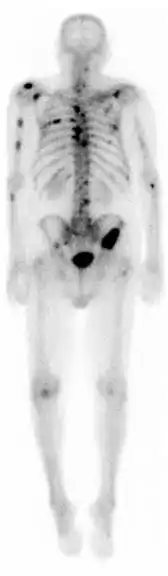

Knogleskintigrafi

Knogleskintigrafi er en nuklearmedicinsk metode til at vurdere sygdomme eller tilstande i skelettet. Ved at sprøjte et radioaktivt sporstof ind i en armvene og efter et stykke tid måle og visualisere optagelsen i skelettet og eventuelt bløddele ved hjælp af et gammakamera, kan sygdomsprocesser identificeres og vurderes. Knogleskintigrafi er velegnet til at påvise spredning af kræftsygdomme til knoglesystemet. Dette gælder blandt andet blærehalskirtelkræft og brystkræft. Knogleskintigrafi kan også anvendes til at påvise en bred vifte af led- og knoglesygdomme (inklusive infektioner i knogler og led) samt stofskiftesygdomme (bl. andet D-vitaminmangel og forhøjet stofskifte). Knogleskintigrafi kan også anvendes til at påvise betændelsestilstande som f.eks. Charcotfod.